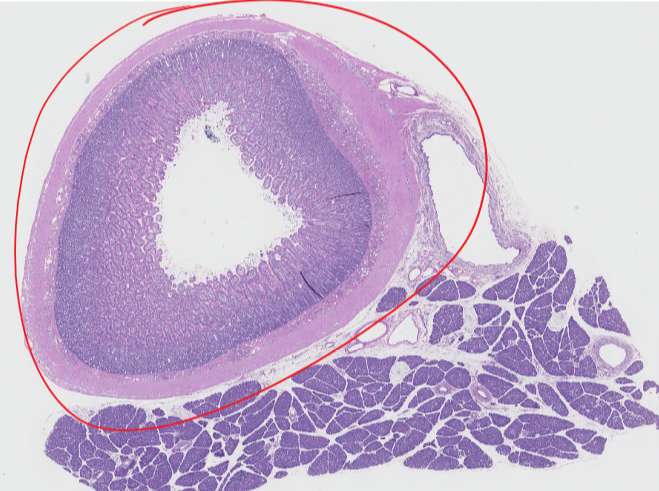

Identify this structure:

piece of the bladder

Q

ureter

transitional epithelium